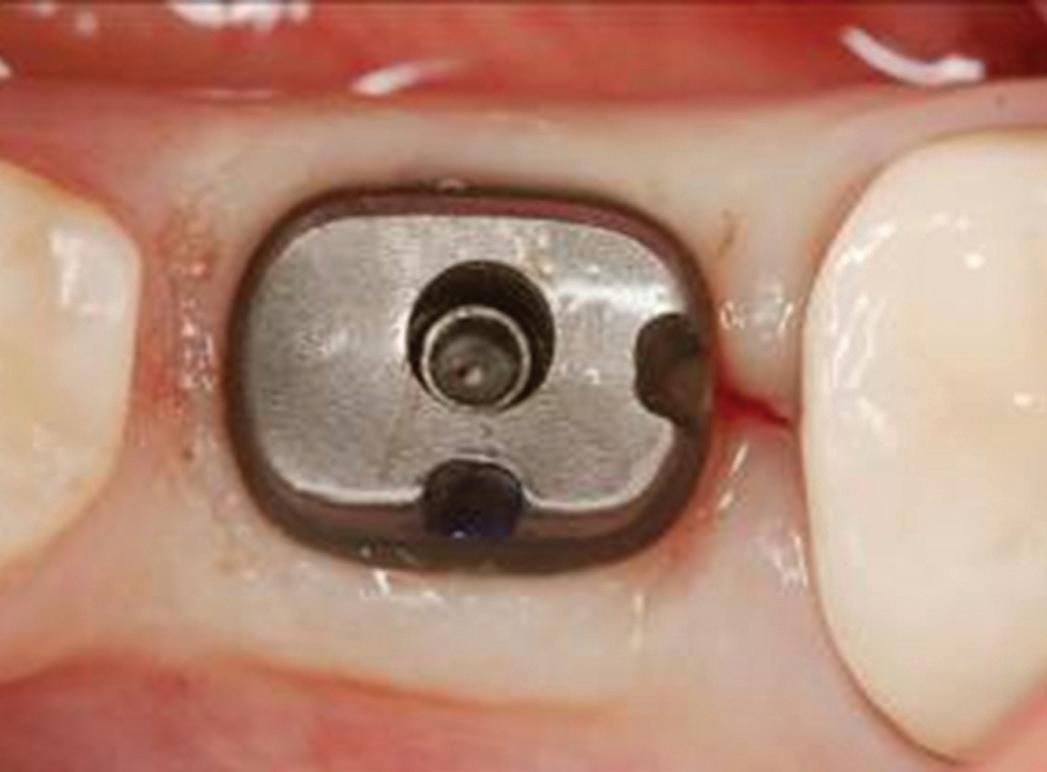

If no perforation is present, the implant is placed in the ideal positioning determined from the preoperative planning (Fig 7). The implant handpiece is preferred for placing the implant fixture because it provides a torque reading in real time as the implant is being placed. The implant motor is electively set to 35 N/cm, and the handpiece will stop advancing the implant once it reaches that reading. The hand driver is then used to finish fully seating the implant at

Fig 7. The implant positioning confirms excellent buccal bone width that will promote long-term stability.

Fig 8. The implant site is closed with PTFE sutures in a 2-stage approach.